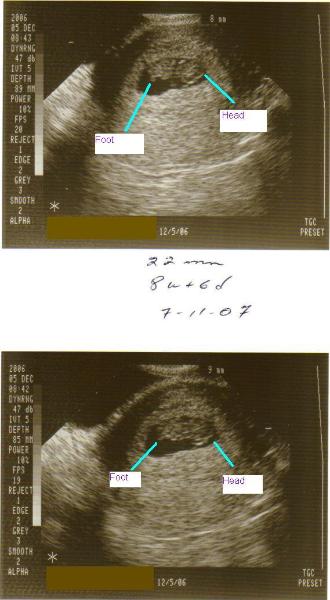

5-30-07

We finally had an ultrasound!!  If you want to

know the results,

click here.  Otherwise, the

baby is looking just fine.  We're within three

days of our due date, size-wise, so that's good

news!  My blood sugar has been really good,

now that I've figured out what to eat and when.

So we have about six weeks left until baby #2

arrives!  Here are some more baby pictures.

There are also pictures on the page linked

above, but only click that if you want to know

the sex!

Click here for the video of the

ultrasound.